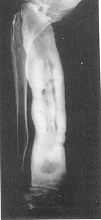

SIFILISUL CONGENITAL TARDIV apare la vârsta de 5-6 ani, se localizeaza predominant la tibie

osteita osifianta - tibie în iatagan

osteita rarefianta - gome sifilitice

forma mixta